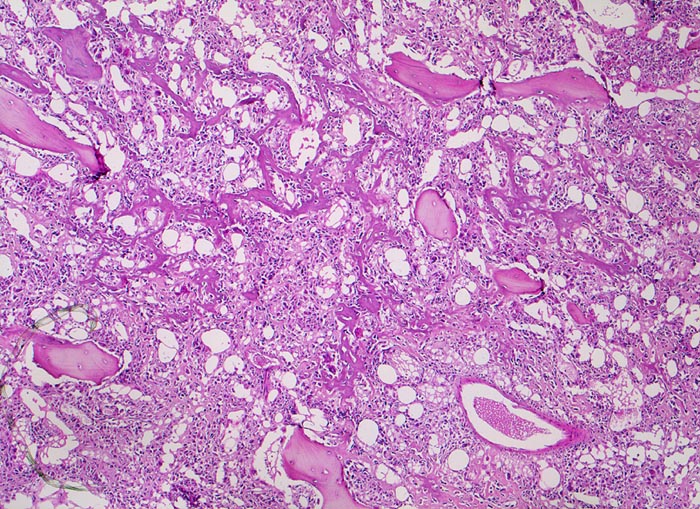

Osteosarkom

maligner Tumor

Knochen, Femur

Die breiten ursprünglichen lamellären Knochenbälkchen sind weitgehend erhalten. Das von den atypischen Tumorzellen gebildete unregelmässige und fein vernetzte Tumorosteoid liegt in den Markräumen und lagert sich teilweise dem ortsständigen Knochen an.

16 jähriger Jugendlicher mit seit mehreren Wochen bestehenden belastungsunabhängigen Schmerzen im distalen Femur rechts oberhalb des Knies (Metaphyse). Im Röntgenbild irreguläre Verdichtung, zum Teil auch Aufhellung der ursprünglichen Knochenstruktur mit Zerstörung der Corticalis und spiculaartige (=sonnenstrahlenähnliche) Periostreaktion. Im Serum erhöhte alkalische Phosphatase.

Histologie

50